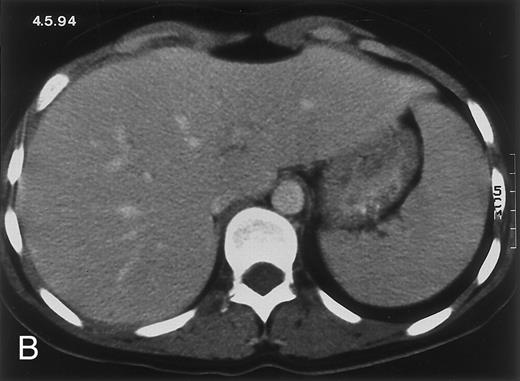

(C) On June 6, 31 days after normalization of neutrophils, CT again shows multiple lesions in the liver (arrowheads) with a different presentation: the small lesions show strong peripheral enhancement. (D) On September 2, 129 days after neutrophil recovery, all hepatic lesions have completely resolved.